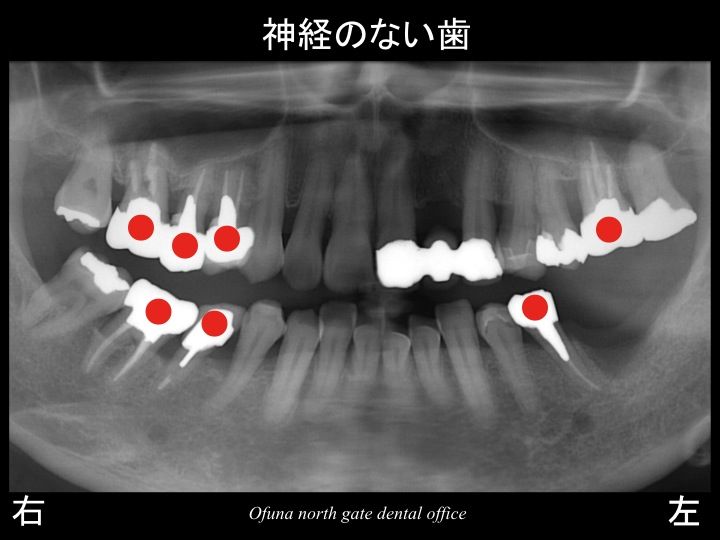

以下の赤丸(●)が神経がない歯です。

欠損部手前の歯は、

神経がないこと、

歯が斜めになっていること

を考えると将来的に歯根破折 を起こしてもおかしくない歯です。